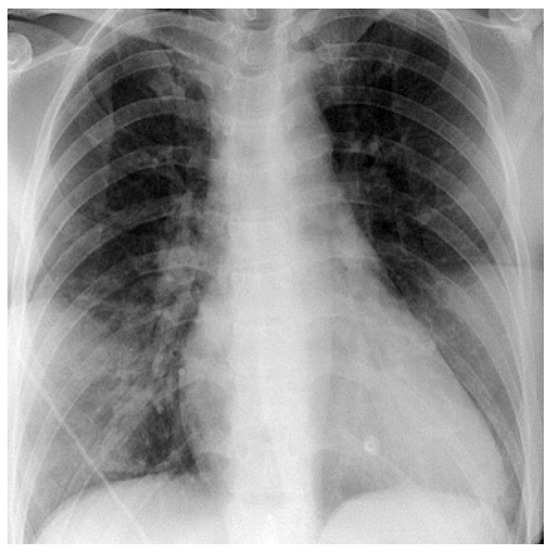

Case 2